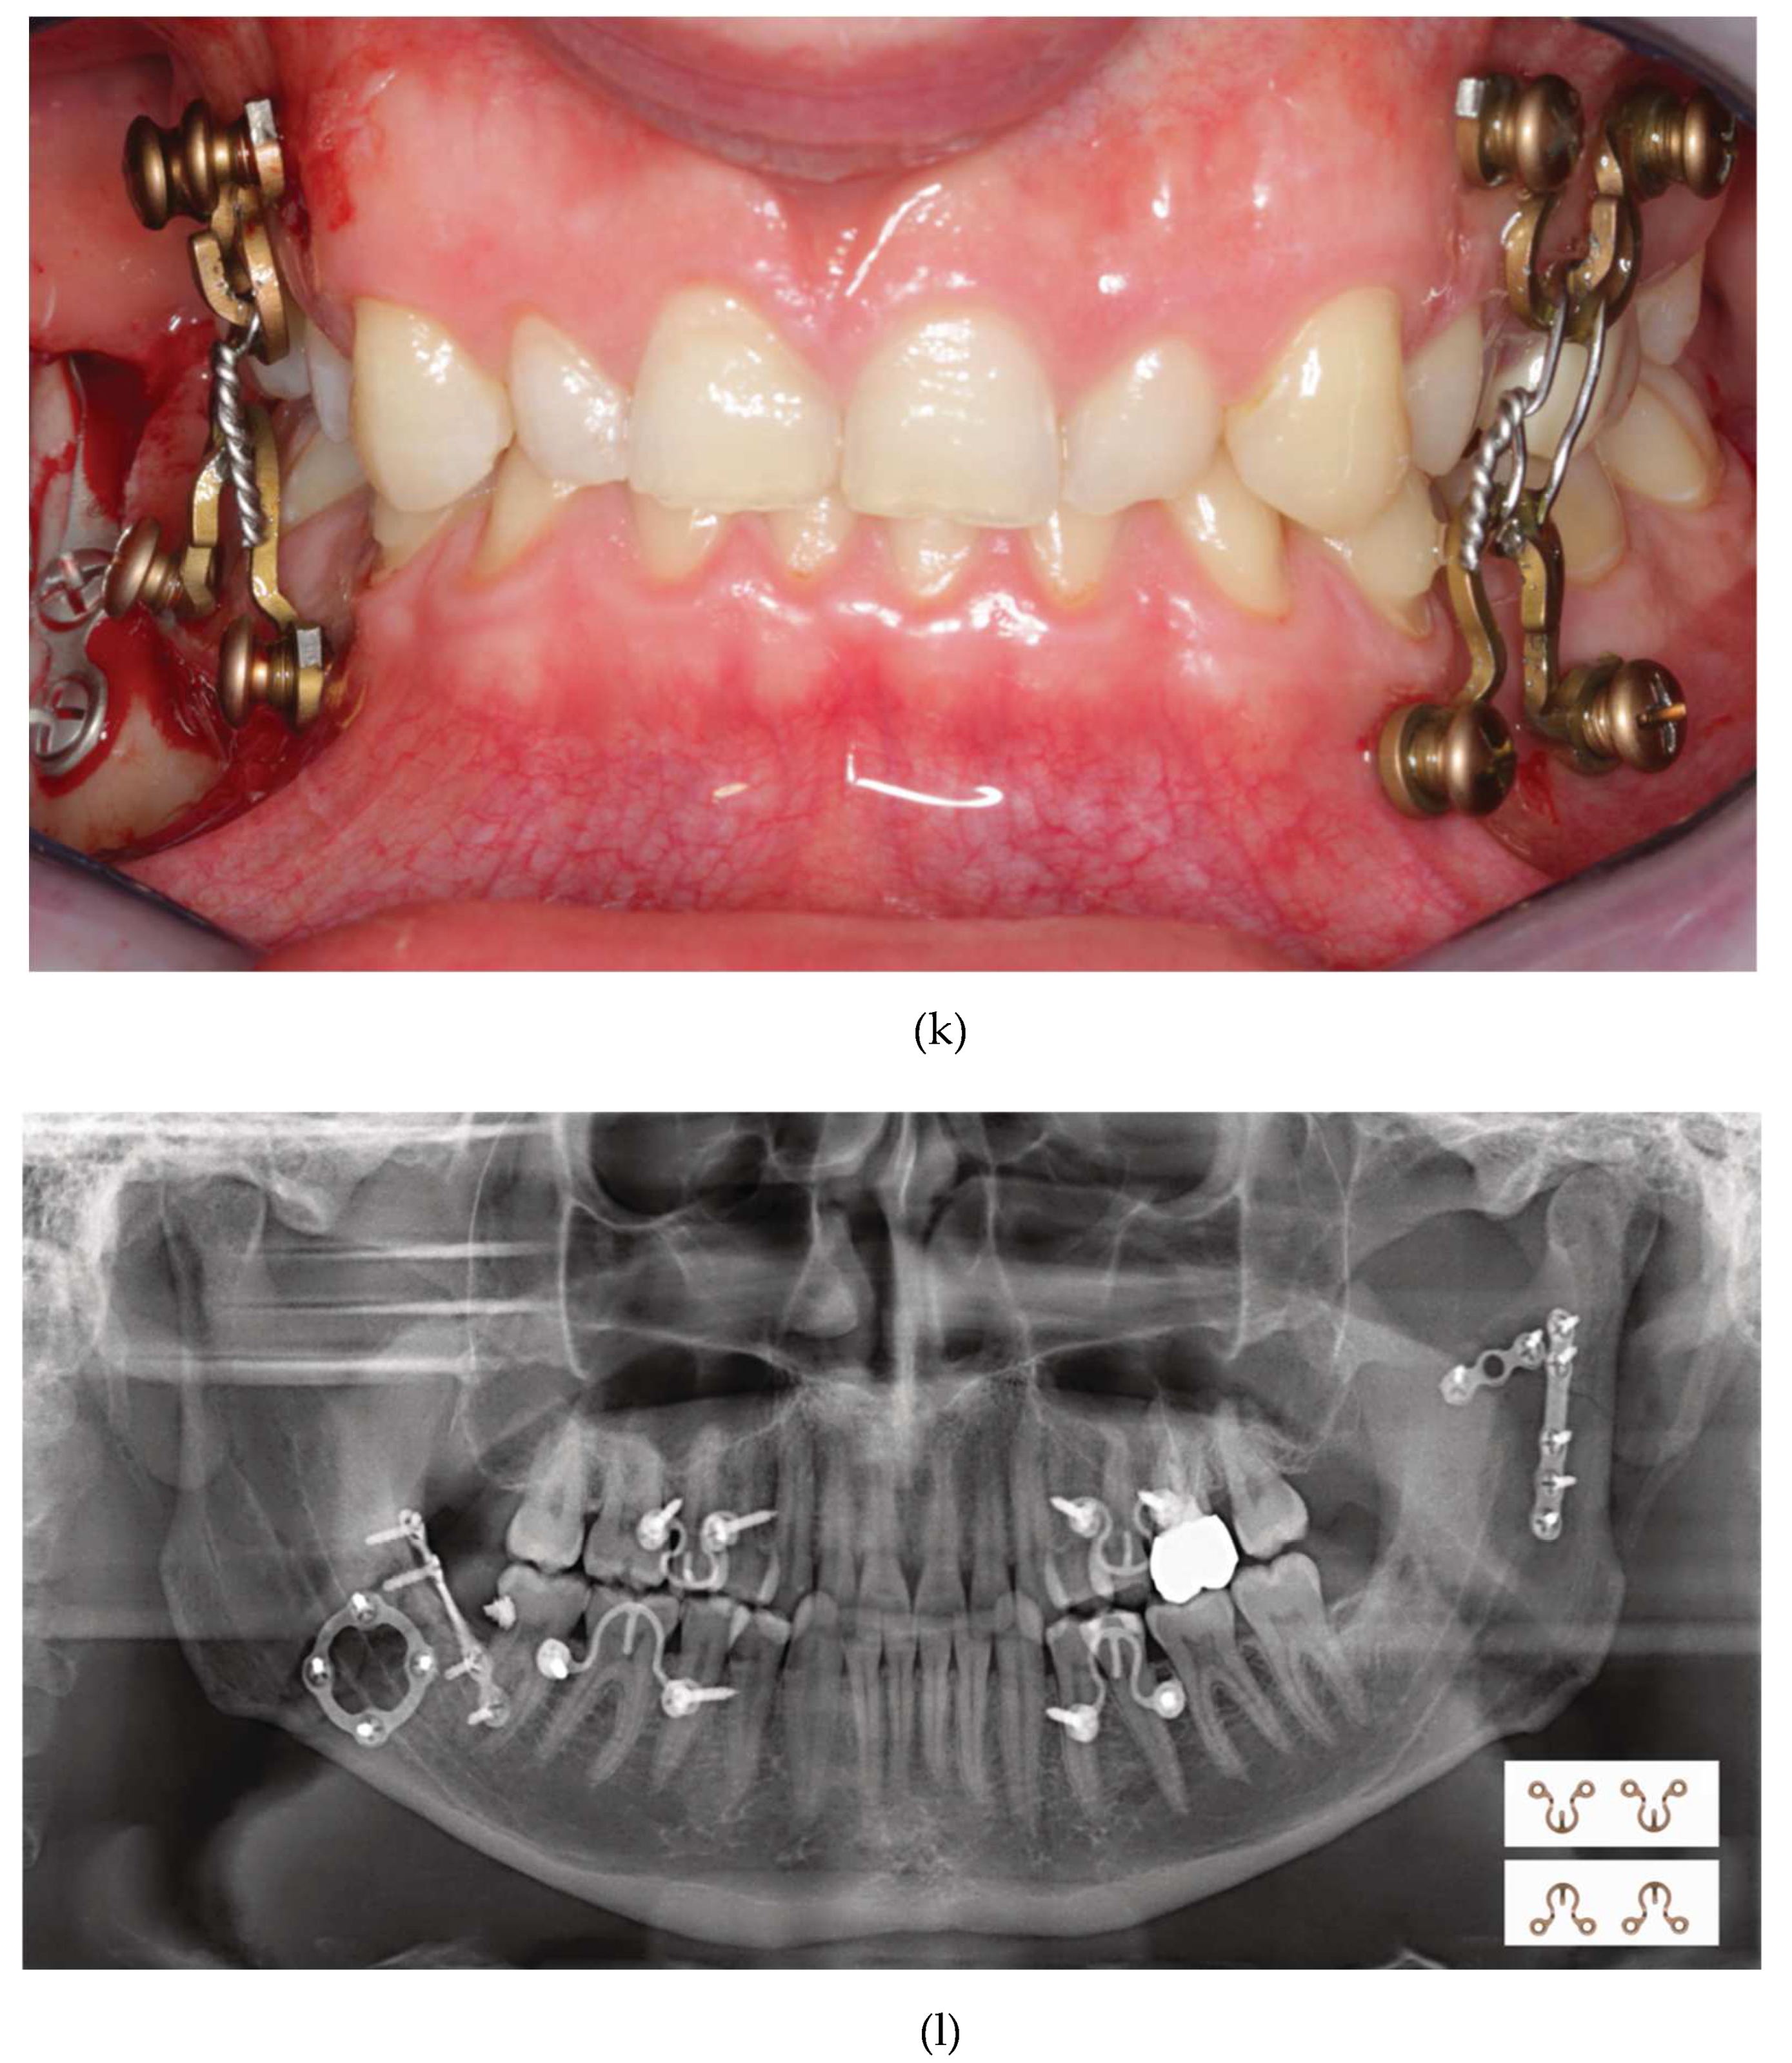

Figure 16 K: MWP Omega segments mounted in all jaw quadrants for temporary intraoperative MMF with wire ligatures to immobilize the mandible. Note: Conical locking heads are partially countersunk, only.

Figure 16 L: Postoperative Panoramic x-ray after transoral ORIF (miniplate osteosynthesis). 4 MWP segments left in place for optional functional treatment during follow-up. All screws for MWP attachment located in interradicular alveolar bone Inset: four MWP Omega segments as oriented and used in this illustrative case.